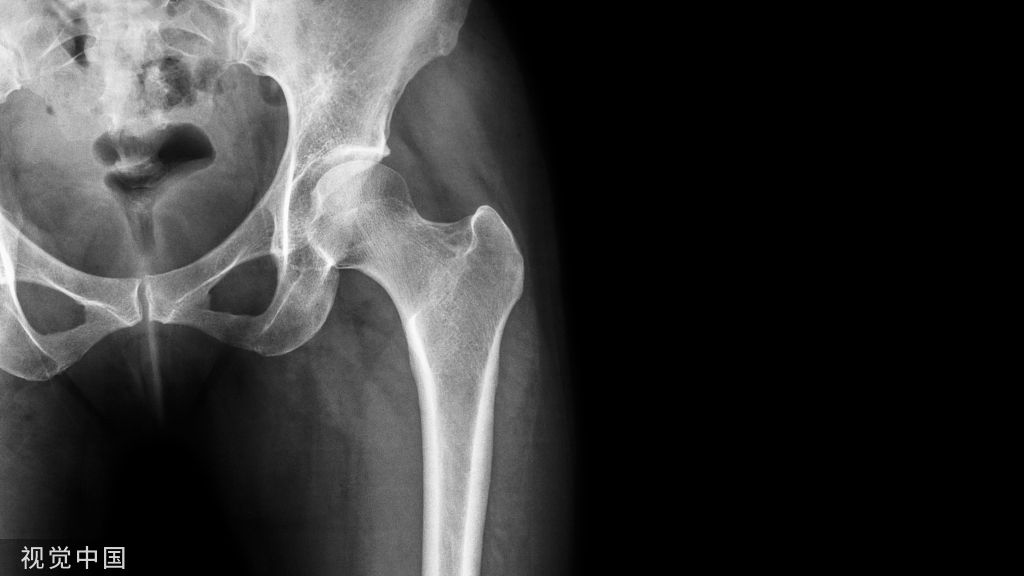

今天是腕部与手的X线片。所有X线片都

带有标注和说明

,可以选择长按图片,

自动翻译相关说明